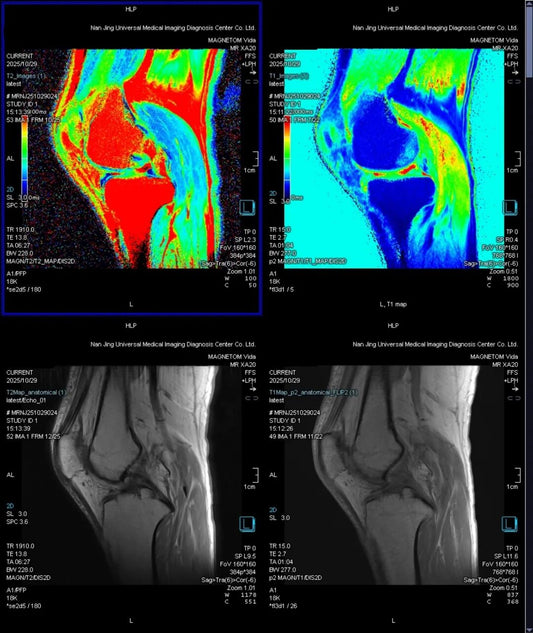

From Morphology to Composition: Beijing Radiology Team Achieves Pixel-Level "Biochemical Auditing" of Cartilage via $T_{2}$-Mapping.

Using $3.0T$ quantitative MRI ($T_{2}$-Mapping & $T_{1}$ Map), the Beijing Radiology Expert Team successfully localized "invisible" lesions by measuring biochemical shifts in the cartilage matrix, establishing a digital baseline for...